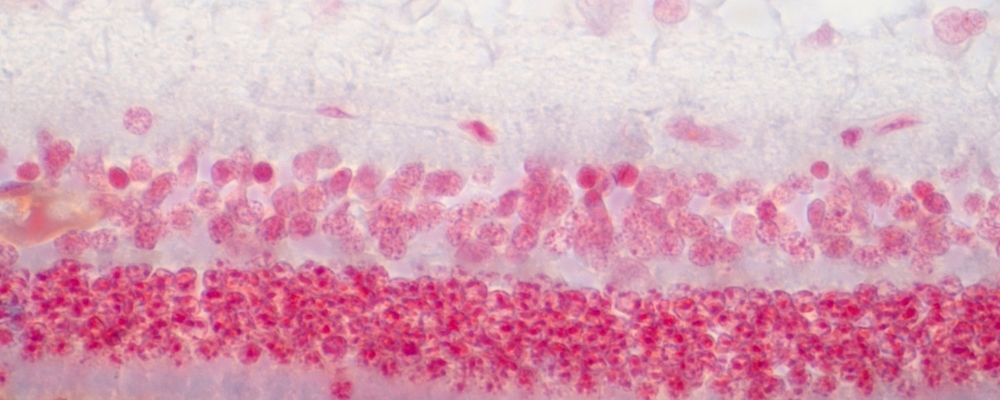

Guided Tissue Regeneration (GTR) is an advanced periodontal procedure used to help restore bone and supporting tissues that have been damaged by periodontal (gum) disease. At Mayflower Periodontics & Implant Center, GTR is performed to encourage the body’s natural ability to regenerate lost tissue and improve the long-term stability of your teeth.

During the procedure, a specialized barrier membrane is placed between the gum tissue and the affected area of bone. This membrane protects the healing site and allows bone and connective tissue to regenerate while preventing unwanted tissue from interfering with the healing process.